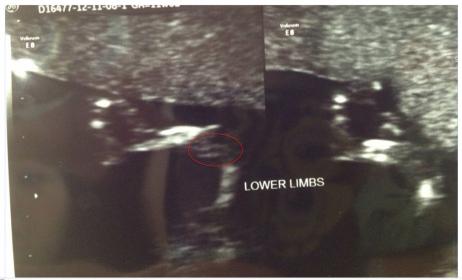

Hi girls, here is a pic that I think might be nub? The tech refused to give me any potty shots or nub shots but I think this one might show it?

Have a couple more and will post later but I think this is the clearest. Would love to know your guesses please :)